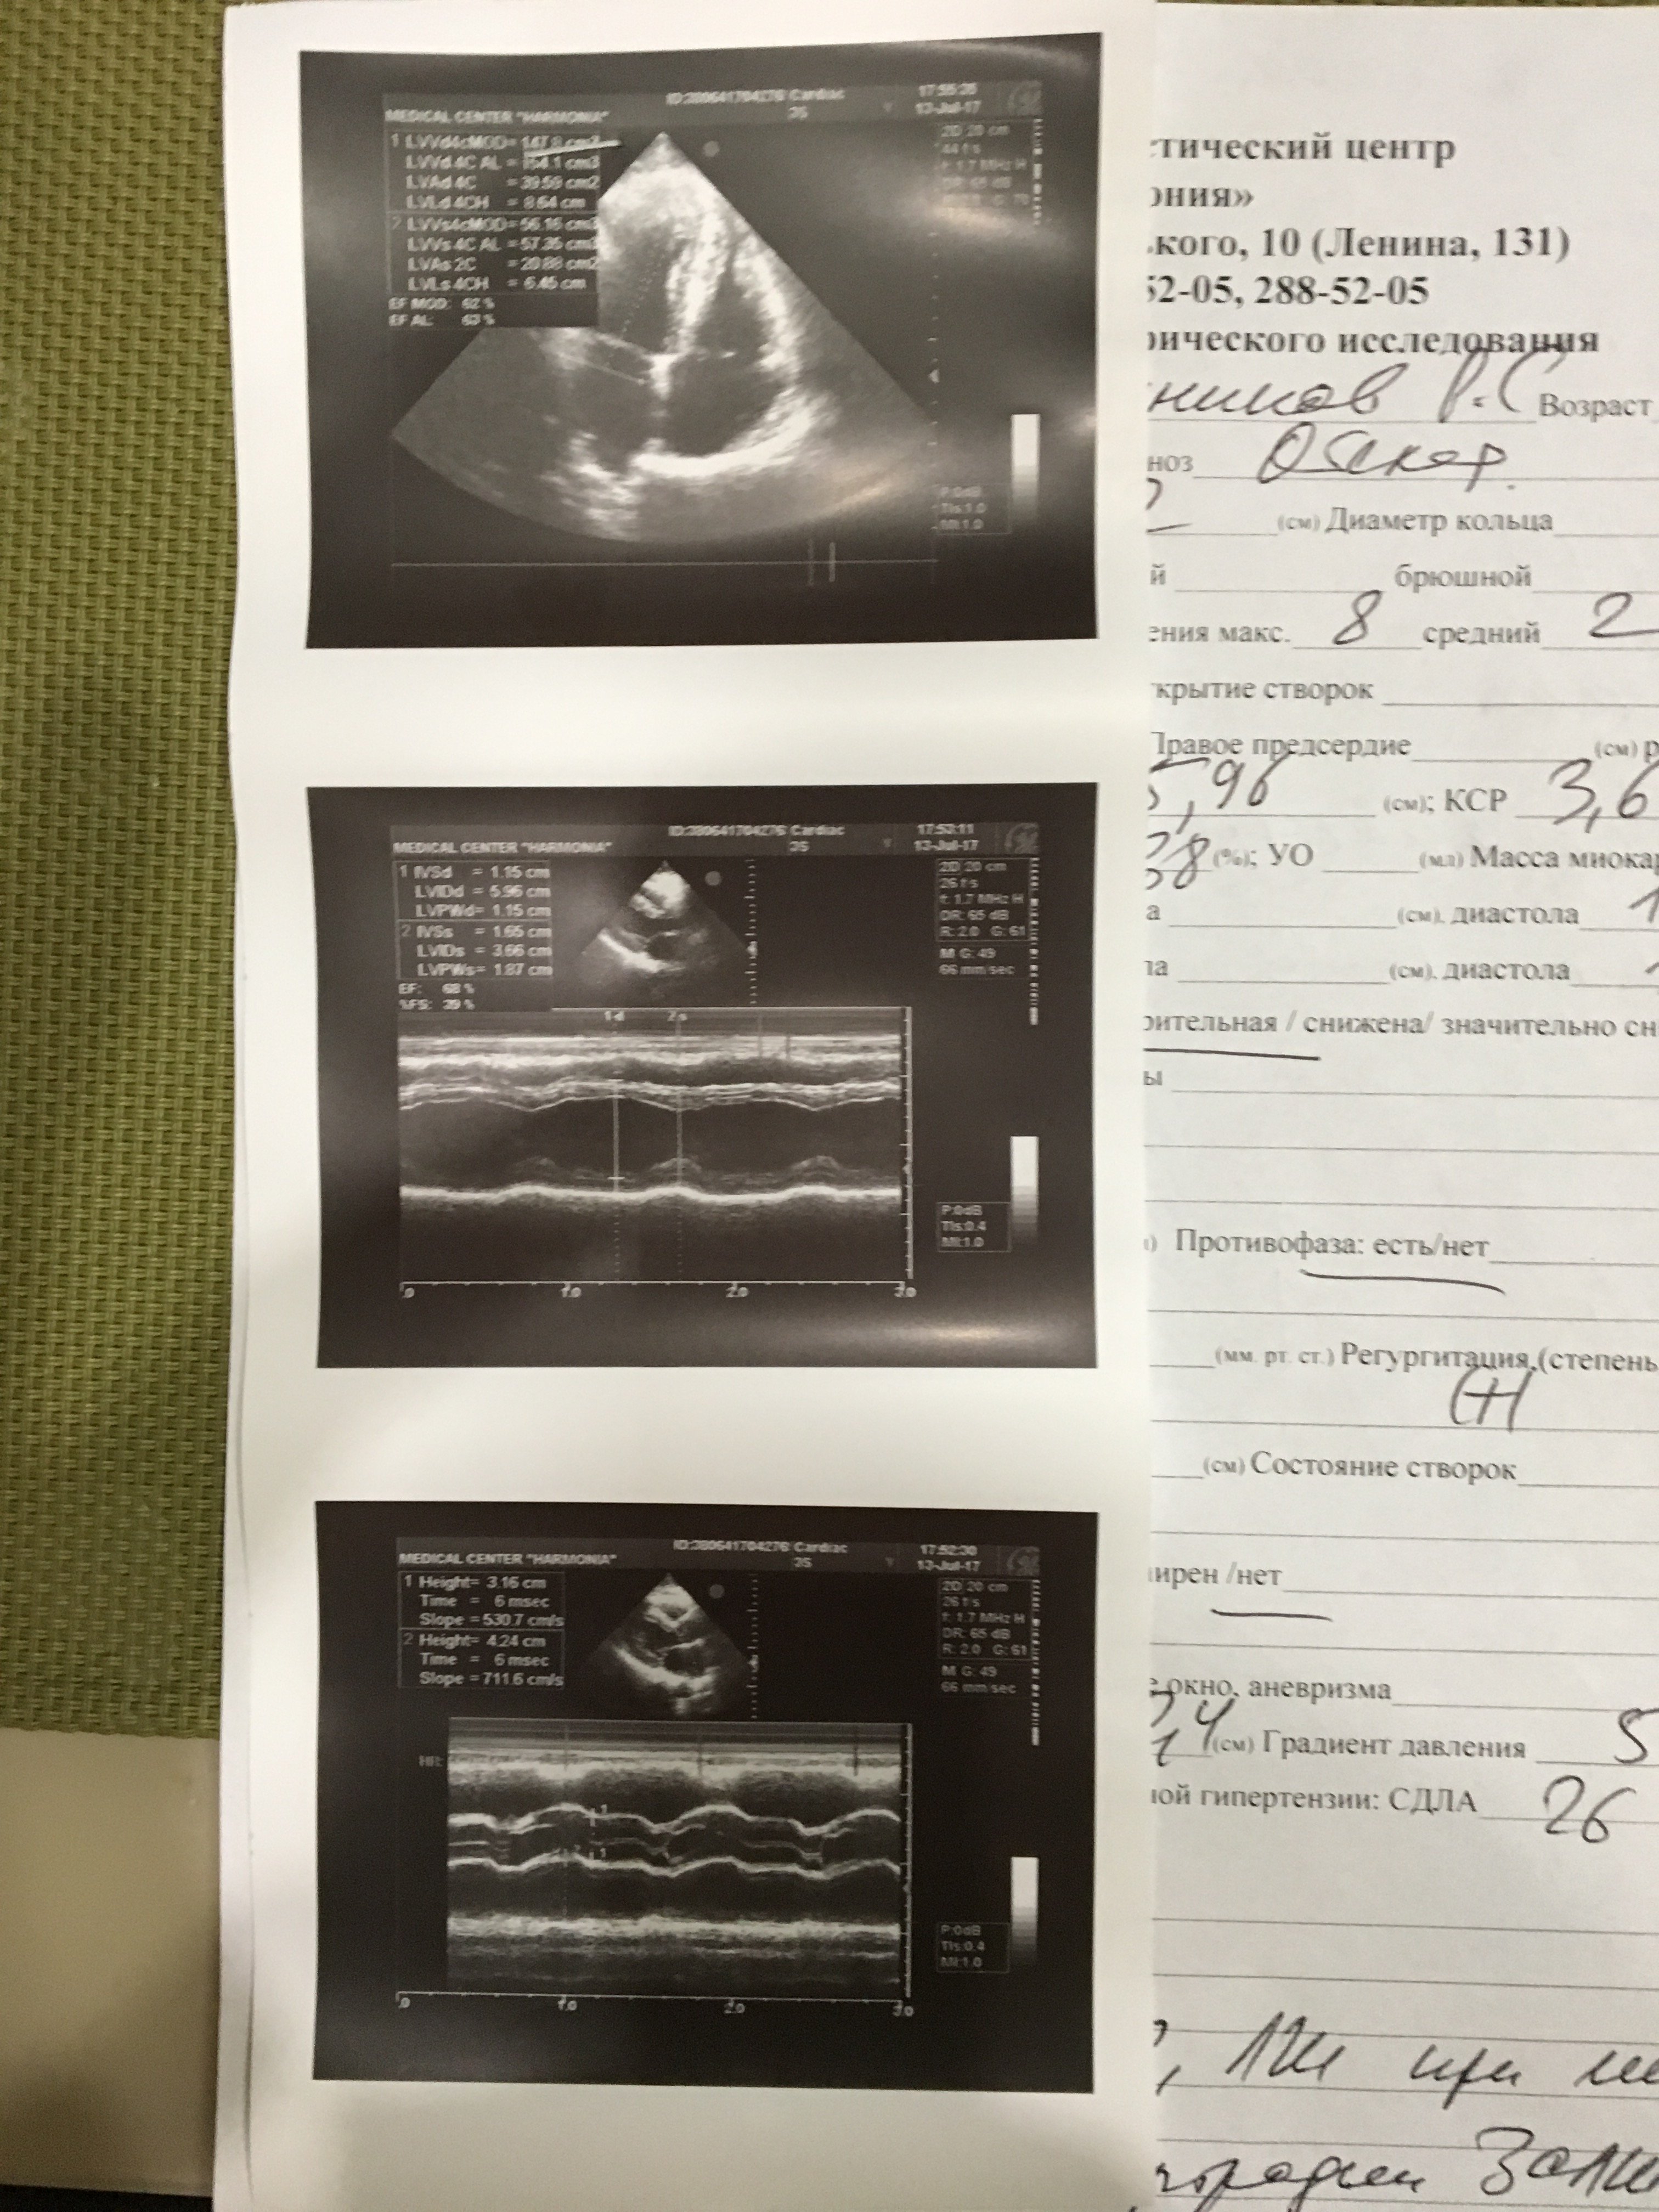

Ветка спортивного кардиолога